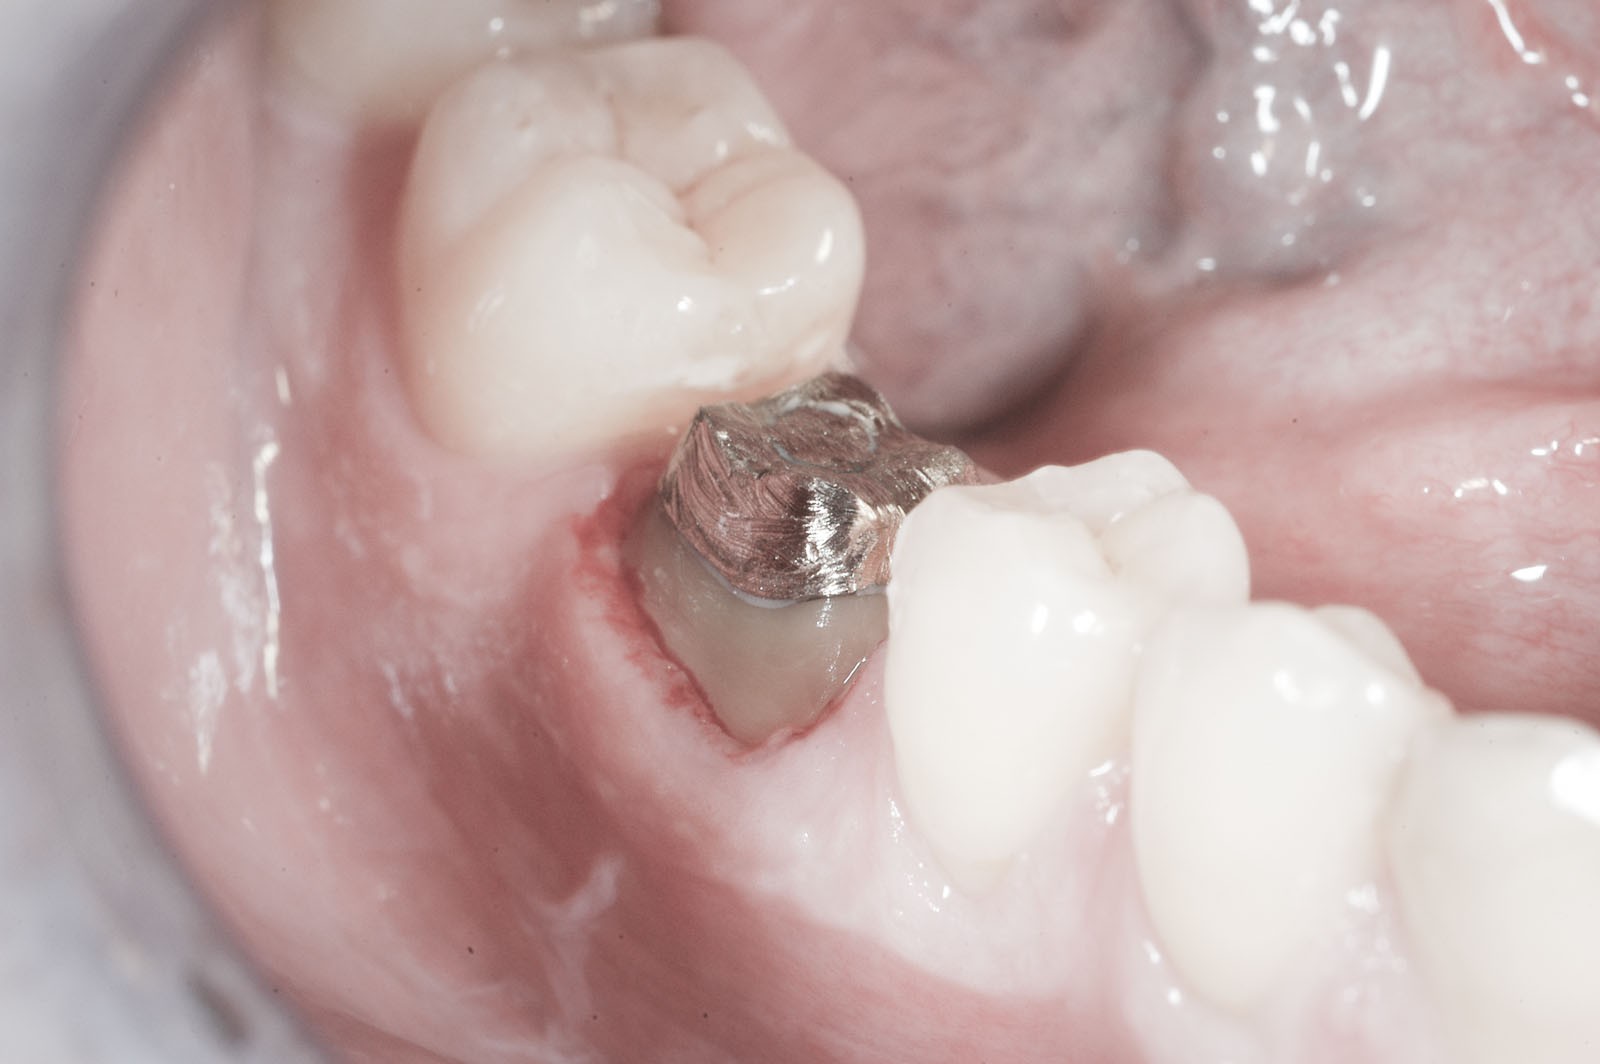

Korona protetyczna ma za zadanie odbudować zniszczoną część naddziąsłową pojedynczego zęba. Przy dużej destrukcji twardych struktur zębowych często wykonanie korony powiązane jest z leczeniem endodontycznym. W sytuacji dużych zniszczeń części koronowej zęba i słabej retencji dla przyszłej korony protetycznej dodatkowo ząb powinien zostać wzmocniony wkładem koronowo-korzeniowym indywidualnie odlewanym ze stopów metalu w laboratorium lub gotowym, wykonanym z włókna szklanego. Wkład koronowo-korzeniowy cementuje się w kanale korzeniowym po prawidłowo przeprowadzonym leczeniu kanałowym.

Wkłady koronowo-korzeniowe to rusztowanie dla korony zęba. Ich zadaniem jest jego wzmocnienie. Stosuje się je w zębach leczonych kanałowo, w których doszło do dużego zniszczenia struktur korony zęba.

Wskazaniem do wykonania wkładów koronowo-korzeniowych jest wzmocnienie zęba leczonego kanałowo, w którym doszło do powstania dużego ubytku w jego części koronowej. Jeżeli ząb ma niewiele tkanek własnych lub są one uszkodzone, grozi to powstaniem naprężeń, w wyniku których może dojść do odłamania się jego ścian. Wkłady koronowo-korzeniowe zapobiegają uszkodzeniom mechanicznym zębów.

- Wkłady koronowo-korzeniowe – przeznaczone dla zębów po leczeniu kanałowym, których konstrukcja wymaga wzmocnienia ze względu na stopień jej uszkodzenia. Wkłady wykonywane są w laboratorium protetycznym lub w gabinecie stomatologicznym i montowane wewnątrz kanału korzeniowego zęba. Wkłady laboratoryjne to indywidualnie odlewane elementy ze stopów metali, podczas gdy w gabinecie używa się wykonanych z włókien syntetycznych.